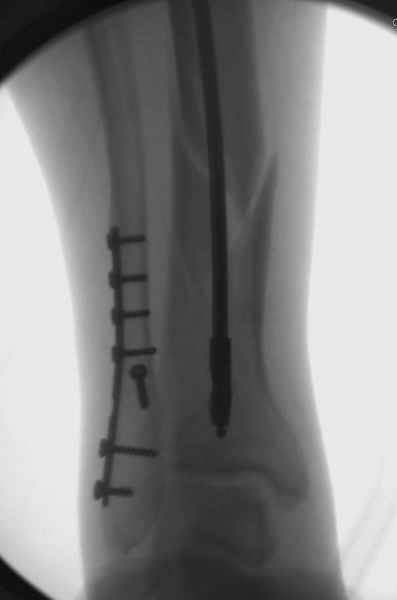

спрашивает что делать с больным который поступил недавно, фермер 55 лет падение при пьяной драке в баре, года два назад перенес операцию на лодыжке, на снимках и КТ перелом без вовлечения сустава,

Повреждение такой локализации, на которой применимы и аппарат (классический Илизарова или гибридный), пластина, особенно Locked Plate, и гвоздь с блокированием. В нашей клинике был бы выполнен закрытый интрамедуллярный остеосинтез. Желательно использовать гвоздь с возможностью провести более чем 2 обычных фронтальных винта в дистальном отломке.

Здесь мы использовали новый Synthes Nail с дополнительными дырками, в проксимальной части 4: по две косых и поперечные (один стандартный а другой динамический), в дистальной части две поперечные, прямая и косая. Вес больного более 120 кг, нагрузку начнем через месяц.

Получилось красиво, поздравляю. Вверху можно было ограничиться одним винтом во фронтальное статическое отверстие, зачем два 45-градусных?

При такий спирали задний край tibia может быть сломан - нет ли этого в данном случае? На всякий случай можно было ввести 1-2 винта 4,5 мм спереди назад мимо гвоздя. Хотя самый дистальный блокирующий винт, возможно, зацепил этот отломок. А какой тут диаметр гвоздя и locking винтов?